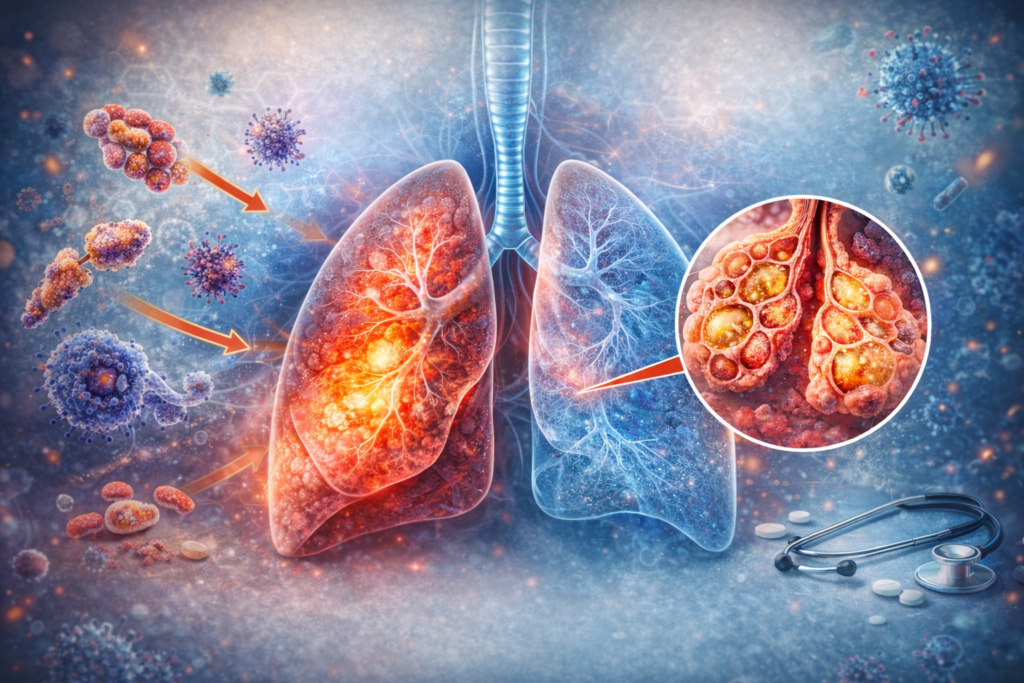

דלקת ריאות היא אחת ממחלות הריאה הנפוצות בעולם – והיא עלולה להיות קלה וחולפת, אך גם מסוכנת ואף מסכנת חיים. מדובר בזיהום ברקמת הריאה שנגרם מחיידקים, נגיפים או פטריות, וגורם להצטברות נוזלים ומוגלה בשקיקי האוויר (נאדיות). כאשר הנאדיות מתמלאות בנוזלים, הגוף מתקשה להכניס חמצן לדם – ולכן מופיעים תסמינים כמו קוצר נשימה, שיעול וחום גבוה. […]